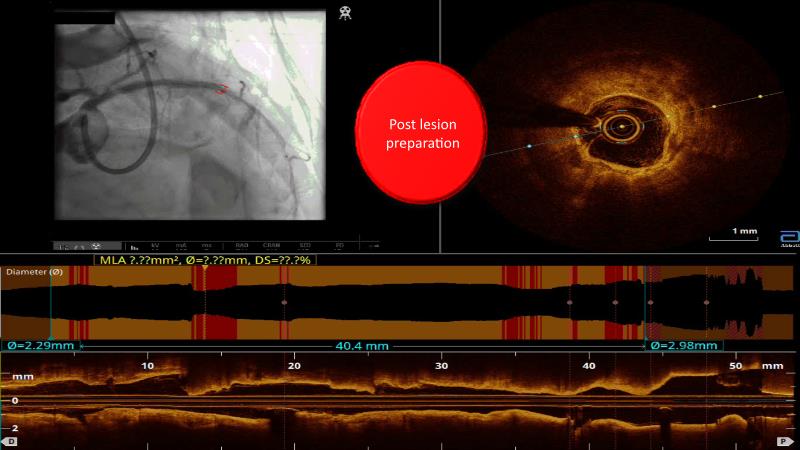

Watch this case-in-point presentation focusing on decision-making in complex PCI using OCT plus AI to understand how to take the right measurement throughout the procedure, how artificial intelligence aids in decision making during imaging-guided PCI, and to gain skills in interpreting OCT imaging, among others!

- To gain skill on OCT imaging interpretation

- To know what OCT images are actionable and how to decide

- To understand how to take the right measurement across the entire procedure

- To learn how artificial intelligence works in support of decision making during imaging-guided PCI